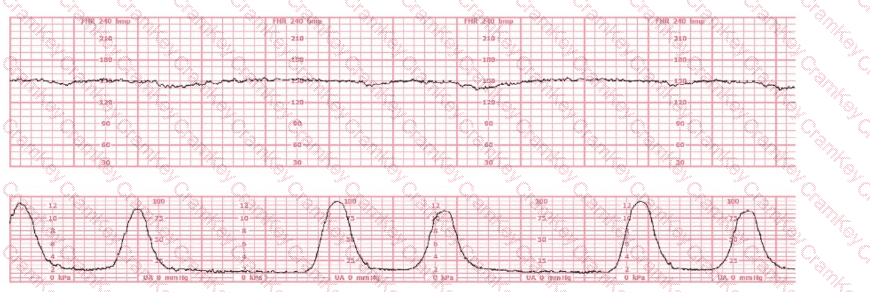

Question 11

The most probable underlying fetal physiologic cause for this tracing would be:

Questions 11

Options:

A.

Myocardial hypoxic depression

B.

Release of catecholamines

C.

Vagal nerve stimulation in response to hypoxemia

Discussion